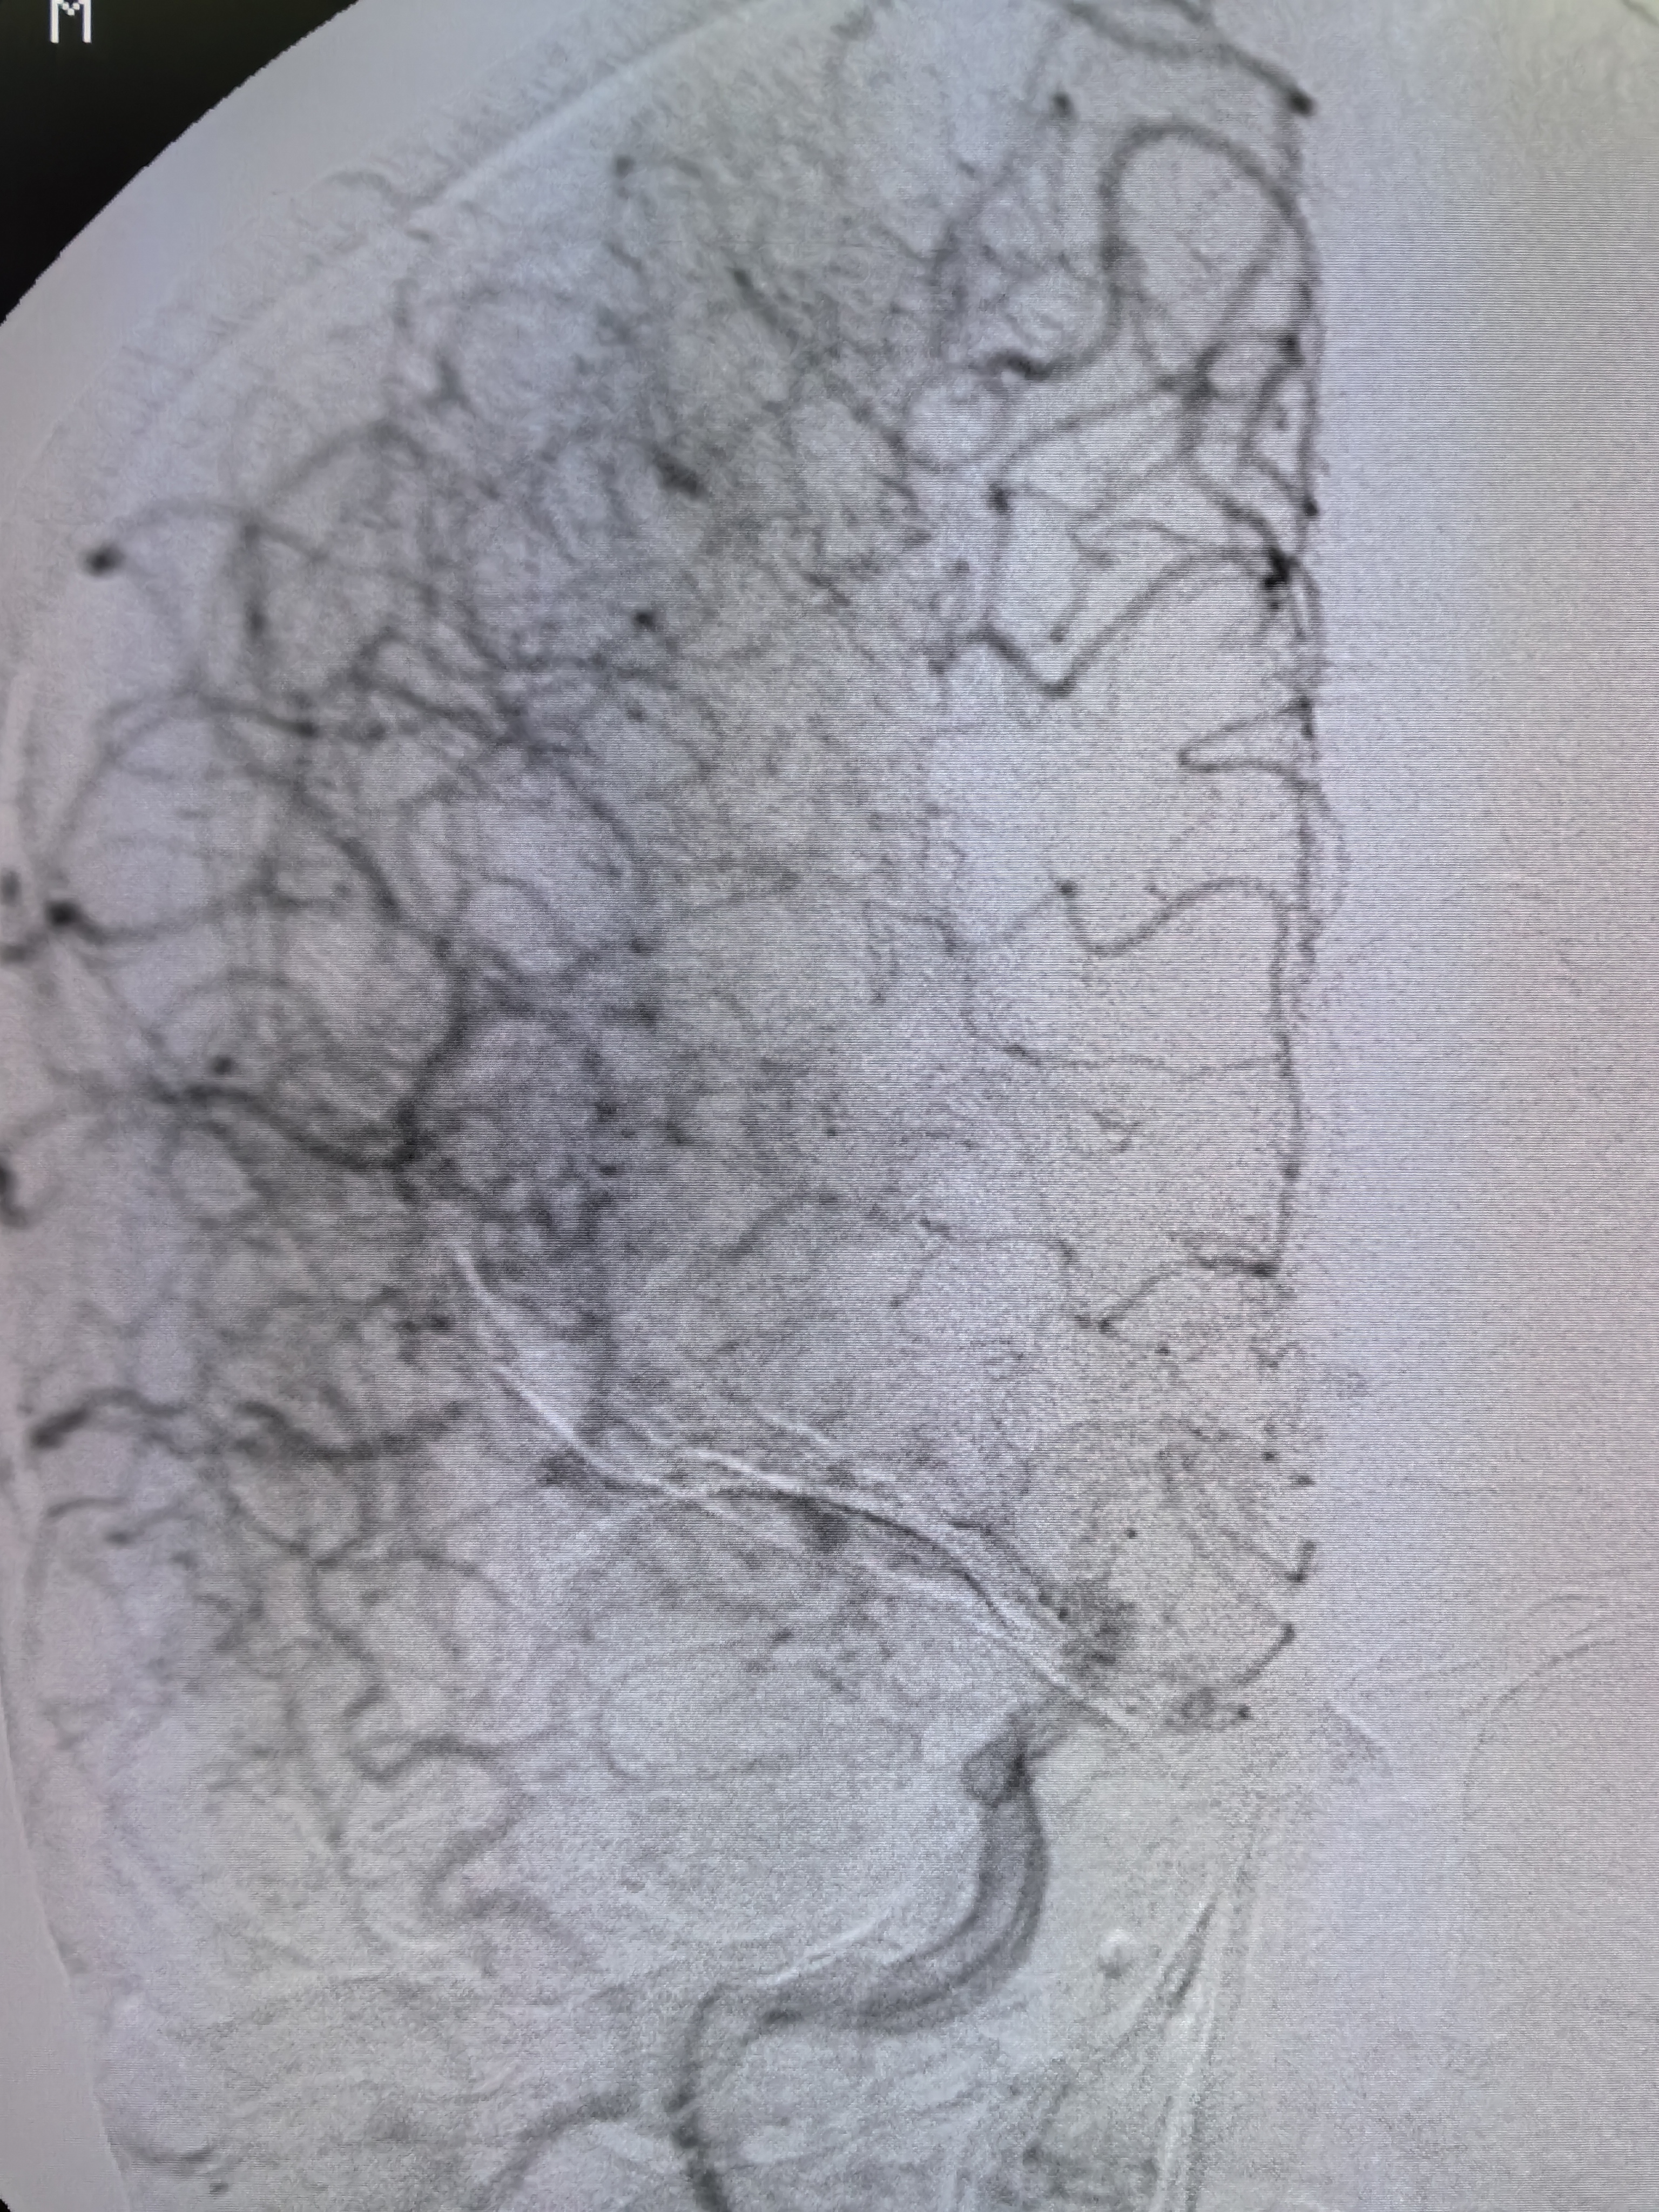

不同凡响|(第152期)老年男性心源性栓塞血管内治疗一例 - 脑医汇 - 神

图片尺寸3072x4096